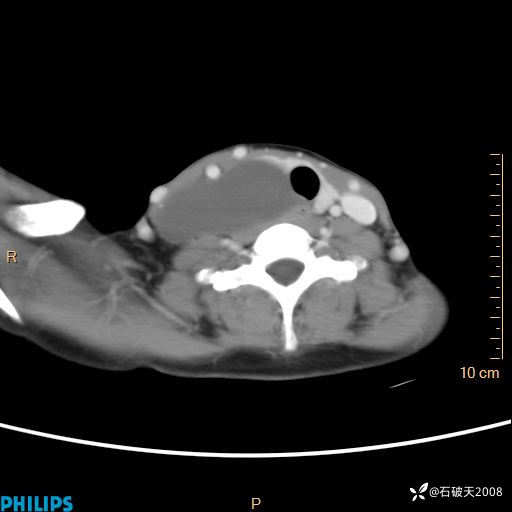

影像诊断要密切结合临床,真的很有必要(病理已公布)

女 21岁 主 诉:发现右侧颈部肿物18年余。

现病史:18年余前患者无明显诱因发现颈部偏右侧有一肿物,具体大小不明确,咳嗽、憋气时肿物增大,局部无疼痛,无吞咽不适,无胸闷及呼吸困难,至当地医院检查考虑良性病变(具体不详)并未做特殊处理,现患者自觉肿物随年龄增长而进一步变大,今日至我院行颈部CT平扫+增强提示:1.右侧颈根部、锁骨上窝及纵隔内异常密度影,考虑良性病变,淋巴管瘤?囊肿?请结合临床。2.双侧颈部小淋巴结。建议结合临床及其他相关检查。现为行进一步治疗,门诊以“颈部局部肿物”为诊断收住我科,发病来患者神志清,精神可,饮食睡眠可,大小便正常,体重无下降。

平扫